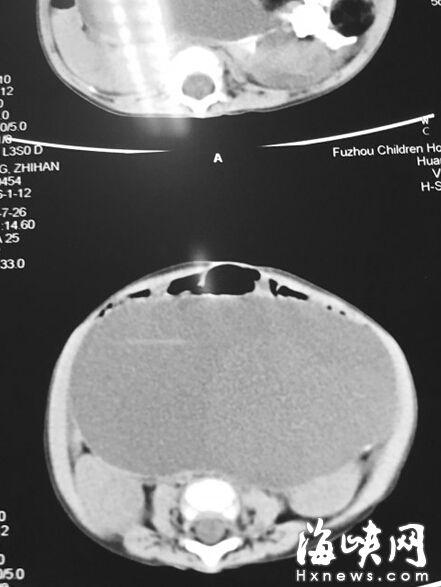

CT顯示,小云腹腔被畸胎瘤霸占

7月22日,家人抱著小云到福州兒童醫(yī)院,福州兒童醫(yī)院副院長、小兒外科學(xué)博士林芃一摸她肚子,推斷可能是巨結(jié)腸或腫瘤。果然,B超結(jié)果顯示,小云 的左側(cè)腹膜后藏著一個巨大腫瘤,被腸管擋住了,為此多次漏診。腫瘤直徑約20厘米,幾乎霸占整個腹腔。7月29日,醫(yī)生花了3個小時剝離腫瘤,其皮質(zhì)硬。 醫(yī)生將瘤中的液體吸出500多毫升,“排球”癟了1/3,才被順利取出。這是一個畸胎瘤,足有2斤重,這么大的很罕見。但畸胎瘤分化不成熟,沒有成形的毛 發(fā)、牙齒等組織,很可能是惡性腫瘤,目前還在等病理報告。